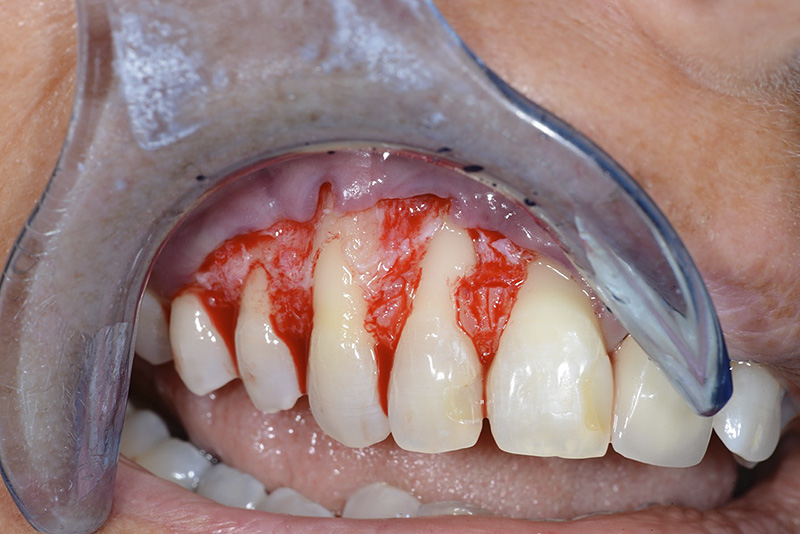

PREMESSA: in seguito all’estrazione dell’incisivo laterale superiore di destra, resasi necessaria per cause batteriche, si decide di affrontare il caso con il posizionamento di un impianto in sostituzione dell’elemento mancante dopo guarigione del sito infetto. Con tecniche rigenerative sia dei tessuti ossei mancanti a causa dell’infezione pregressa, sia dei tessuti gengivali che appaiono inizialmente troppo spostati in alto, si ripristina una corretta morfologia delle parabole (contorni) gengivali e delle papille interdentali (triangoli di gengiva tra due denti vicini).

Vengono utilizzati 2 tipi di provvisori: il primo, cementato ai denti vicini, viene utilizzato dal momento dell’estrazione del dente fino ad impianto osteointegrato (circa 6 mesi); il secondo, avvitato direttamente all’impianto, ha una funzione di prova estetica ma soprattutto di guida per la maturazione dei tessuti gengivali peri-implantari portandoli verso la maturazione completa prima di posizionare la corona finale in disilicato di litio.